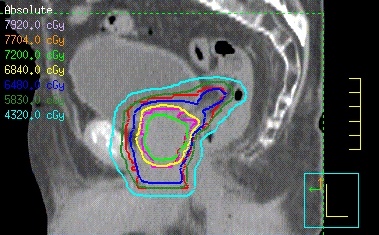

Bei der IMRT erfolgt die Bestrahlung aus mehreren Richtungen, im Gegensatz zur konventionellen Radiotherapie, über eine Vielzahl von Bestrahlungsfeldern. Die Felder werden vor dem Austritt aus dem Bestrahlungsgerät mittels Bleilamellen individuell geformt. Durch die Überlagerung der Einzelfelder aus den verschiedenen Einstrahlrichtungen werden inhomogene Dosisintensitätsverteilungen erzeugt. Das Ziel der Bestrahlungsplanung besteht darin, durch die Verwendung einer Vielzahl dieser inhomogenen Felder in einem Behandlungsvolumen die Dosis der Form des Tumors möglichst exakt anzupassen und empfindliche Organe oder Normalgewebsstrukturen in unmittelbarer Nachbarschaft des Tumors auszusparen. So kann z. B. im Kopf-Hals-Bereich durch eine Schonung einer oder beider Ohrspeicheldrüsen eine dauerhafte Mundtrockenheit vermieden werden.

In anderen Fällen ermöglicht die IMRT bei vergleichbarer oder reduzierter Toxizität eine Dosissteigerung innerhalb des Tumors und damit eine Verbesserung der Tumorkontrolle. So konnte bei Patienten mit Prostatakarzinom in Studien gezeigt werden, dass durch eine IMRT nicht nur die Wahrscheinlichkeit für schwere Nebenwirkungen am Enddarm auf lediglich 1-2 % gesenkt werden kann.